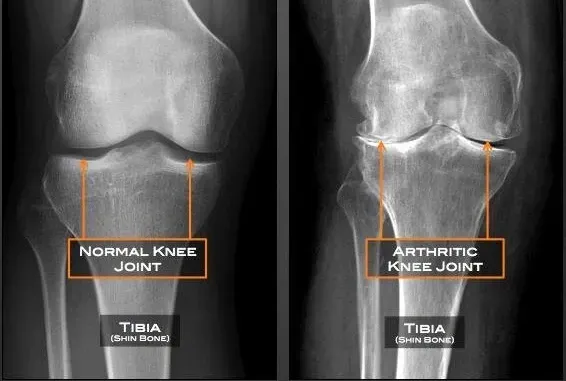

Those diagnosed with osteoarthritis or degenerative joint disease

Patients with bone-on-bone knee issues looking for non-surgical options